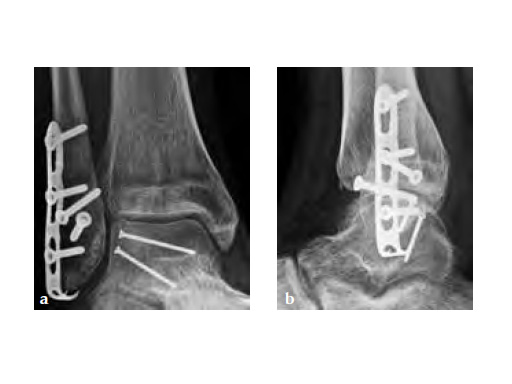

The LCP Hook 3.5 enables tension-band plating with use of 3.5mm screws. The Hook 3.5 was primarily intended for the treatment of simple fractures of the olecranon as well as osteotomies of the olecranon following distal humeral fracture. It has also shown benefits in avulsion fracture of the distal tibia and fibula.

Simple olecranon fractures and osteotomies as well as avulsion fractures of the medial and lateral malleolus treated with traditional tension-band fixation methods are often followed by complications. This is especially evident in patients with poor bone stock and complications include loss of reduction, migration of K-wires and hardware prominence. The LCP Hook 3.5 is a satisfactory alternative fixation.

A 20-year-old construction worker fell from a 3 m height. He sustained a typical posterolateral impression and flake fracture of the talar dome.